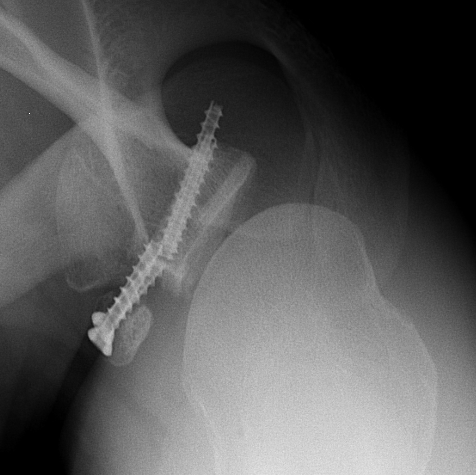

Case 1: Failed Latarjet